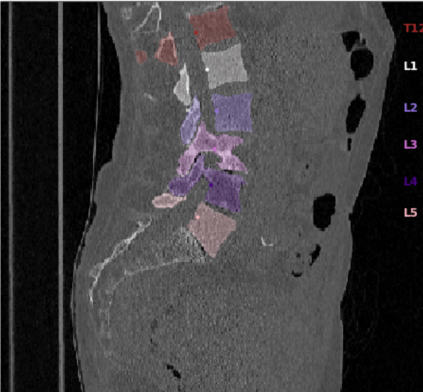

Vertebrae localization, segmentation and identification in CT images is key to numerous clinical applications. While deep learning strategies have brought to this field significant improvements over recent years, transitional and pathological vertebrae are still plaguing most existing approaches as a consequence of their poor representation in training datasets. Alternatively, proposed non-learning based methods take benefit of prior knowledge to handle such particular cases. In this work we propose to combine both strategies. To this purpose we introduce an iterative cycle in which individual vertebrae are recursively localized, segmented and identified using deep-networks, while anatomic consistency is enforced using statistical priors. In this strategy, the transitional vertebrae identification is handled by encoding their configurations in a graphical model that aggregates local deep-network predictions into an anatomically consistent final result. Our approach achieves state-of-the-art results on the VerSe20 challenge benchmark, and outperforms all methods on transitional vertebrae as well as the generalization to the VerSe19 challenge benchmark. Furthermore, our method can detect and report inconsistent spine regions that do not satisfy the anatomic consistency priors. Our code and model are openly available for research purposes.